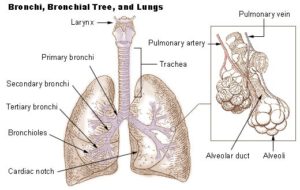

Asthma

Bronchiolitis and Respiratory Syncytial Virus (RSV)

Cystic Fibrosis (CF)